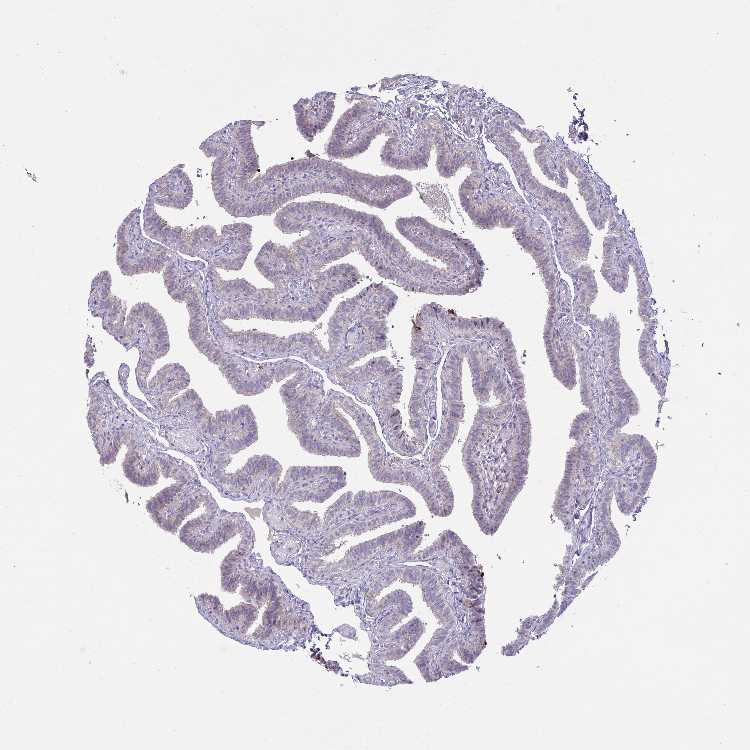

FALLOPIAN TUBE - Antibody stainingi

Antibody staining in the annotated cell types in the current human tissue is reported as not detected, low, medium, or high, based on conventional immunohistochemistry profiling in selected tissues. This score is based on the combination of the staining intensity and fraction of stained cells.

Each image is clickable and will lead to virtual microscopy that enables deeper exploration of all samples and also displays staining intensity scores, fraction scores and subcellular localization as well as patient and tissue information for each sample.

Antibody HPA057763

Glandular cells Medium